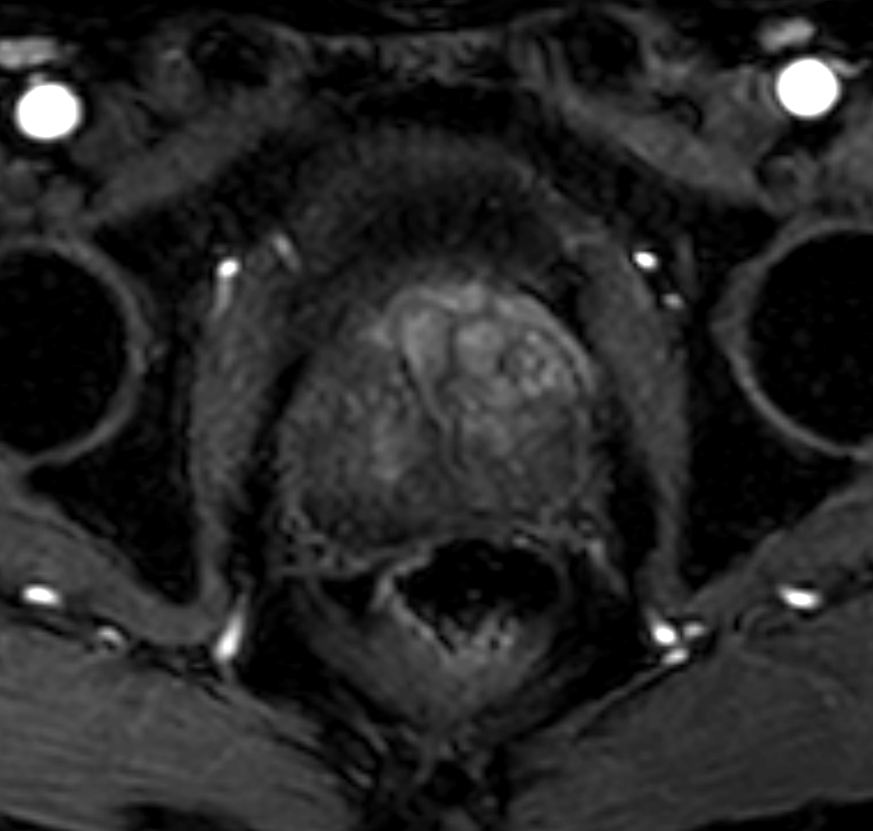

Axial dynamic T1w mDIXON XD - Permeability 48 sec

Axial dynamic T1w mDIXON XD - Permeability 1:08 min

Axial dynamic T1w mDIXON XD - Permeability